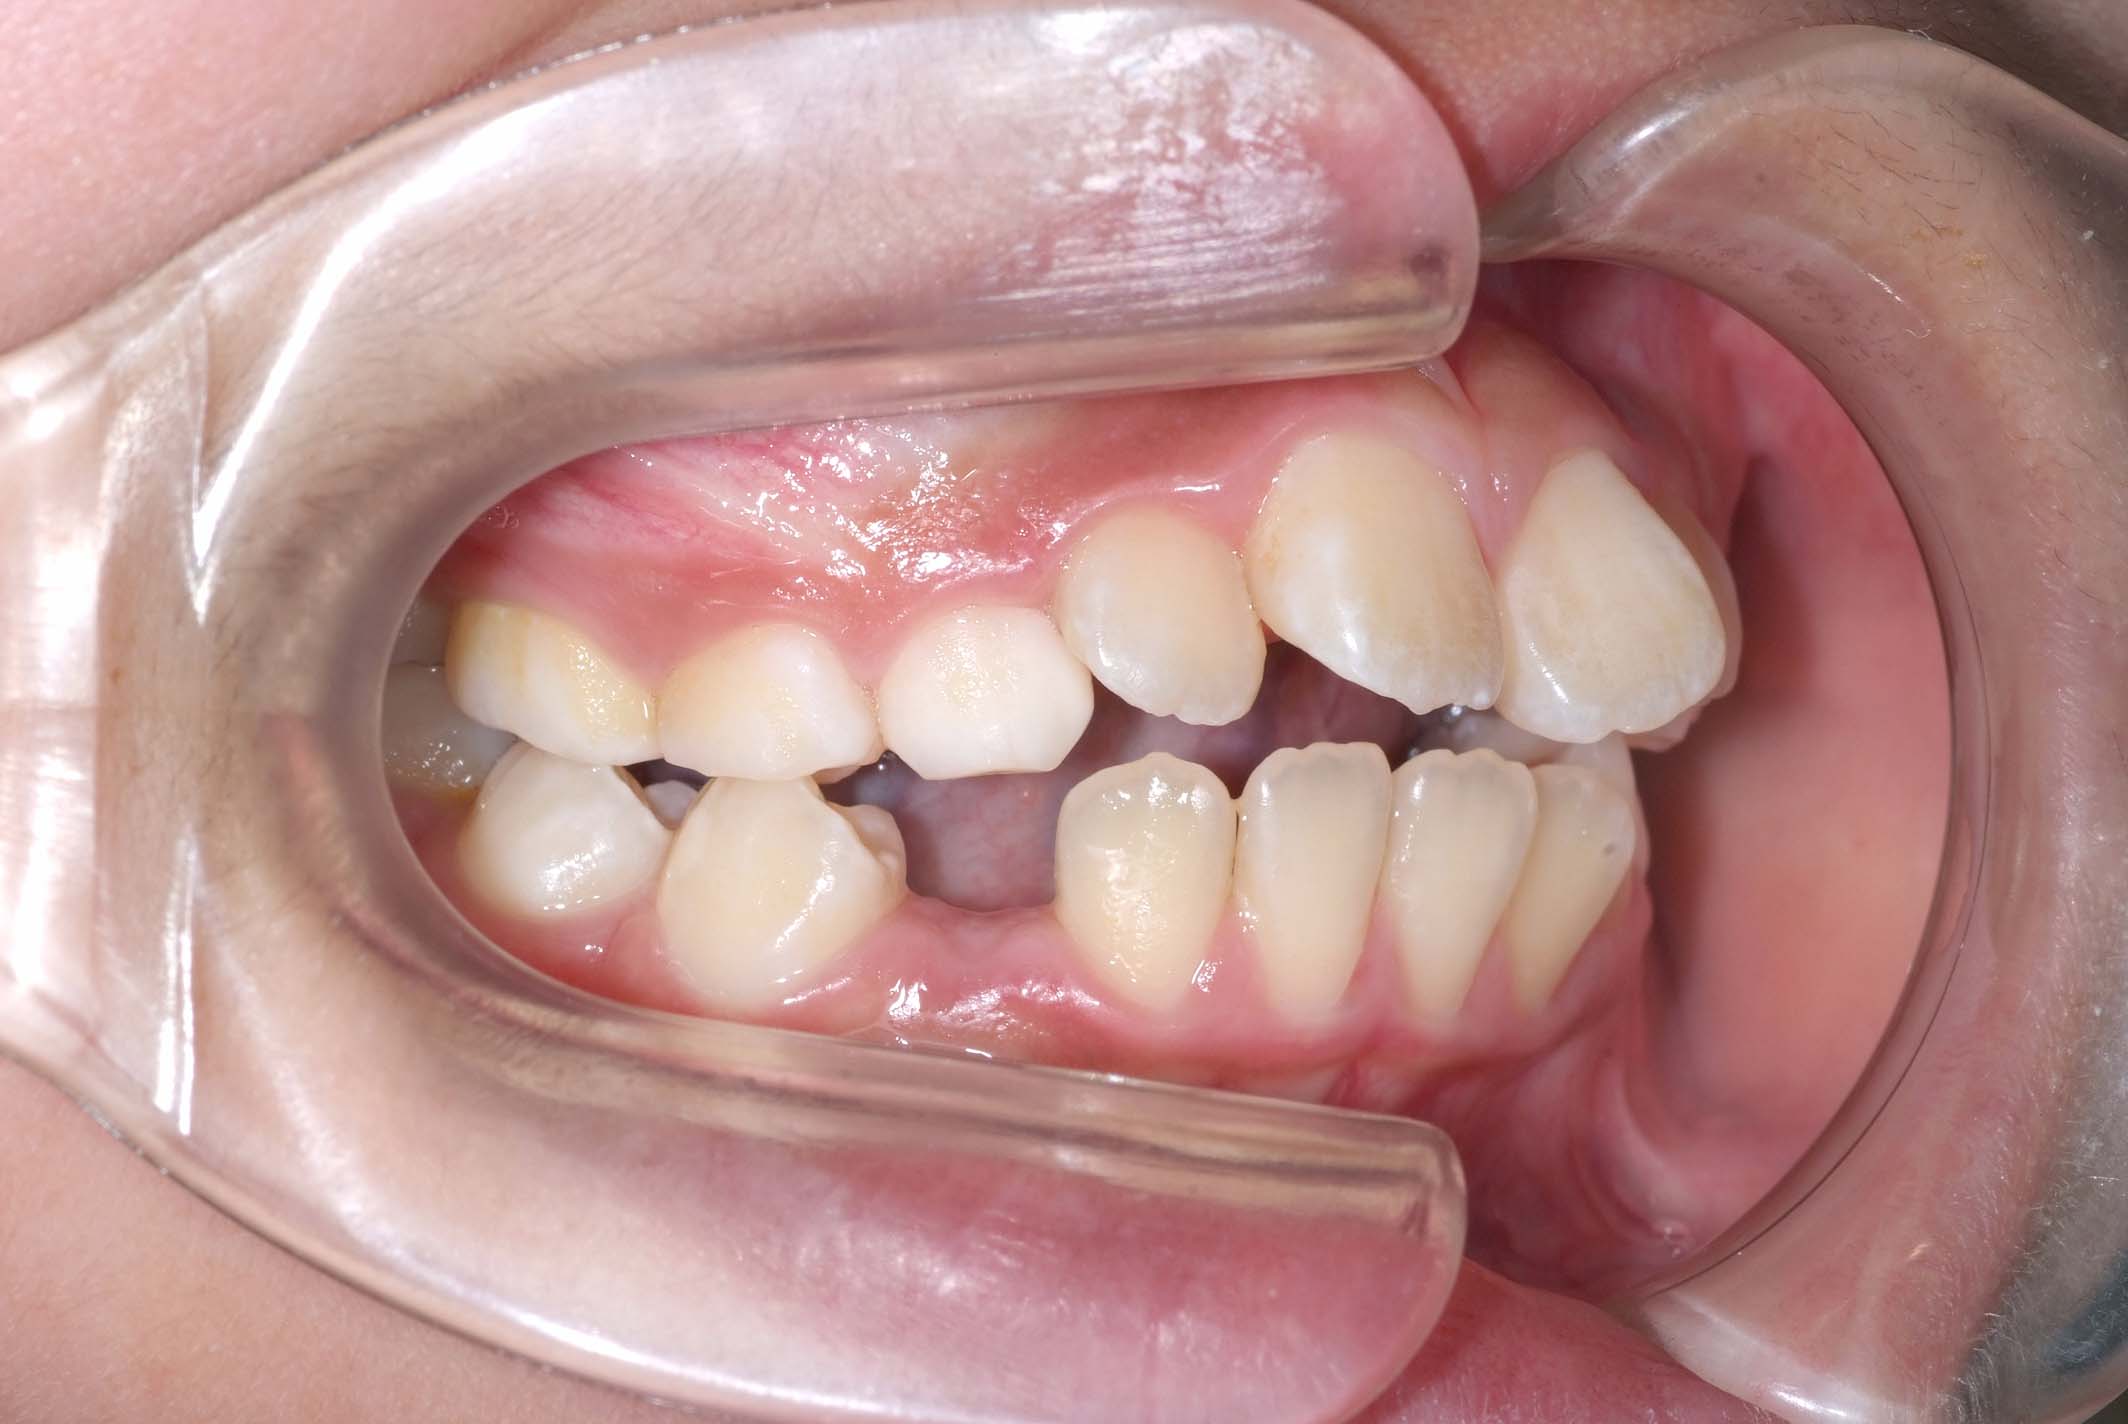

初診時年齢8才の女子で、前歯部開咬を気にして来院されました。

検査の結果、前歯部開咬と正中離開と上下顎前歯唇側傾斜を伴うアングルⅡ級1類不正咬合と診断しました。

前期治療は、リンガルアーチで正中離開を改善し、その後は歯列矯正用咬合誘導装置(マイオブレース)を使用して舌のトレーニングを行いました。後期治療は、上下左右4番を抜歯の上、セルフライゲーションブラケット装置(クリアティ・ウルトラ)で行いました。治療期間は前後期合わせて6年6ヶ月でした。通院回数:60回。